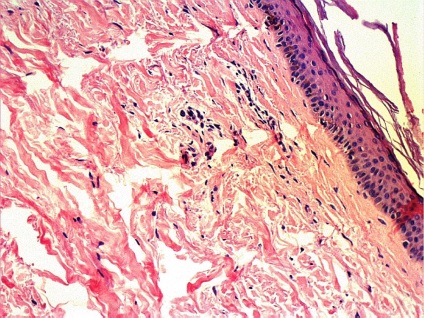

Ábra. 1 Stratifikált hozzáférést az izom, ha teljesítő bőr biopszia

Ábra. 2 futás biopsziát bőrlebenye varrást és az ín izom

Ma már többféle bőr biopszia, köztük - tűbiopszia, excisional biopszia és derma biopszia. Dermatomális és excíziós bőr-biopszia végre az „akut” vagy „nyitott” módon. Amikor egy szikével biopszia dermatomális felületi réteg a bőr, míg a excisional biopszia - kivágtuk nagyobb bőrterületet, majd varrókészülék (fénykép 1). Ugyanezt a technikát használunk, és ha a biopszia musculocutaneous csapóajtót, ha egyidejűleg kimetszett bőr, a bőr alatti szövet és izom lebeny alá.